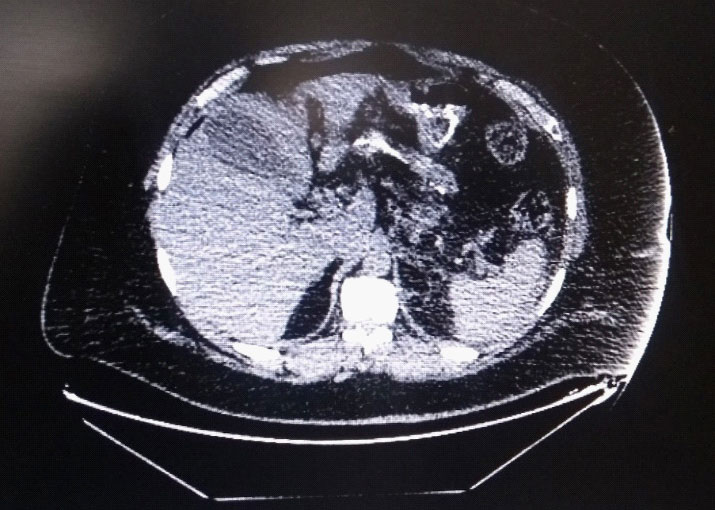

49 yr old gentleman, who underwent Mini gastric bypass for morbid obesity in 2013, presented with chief complaints of pain abdomen since 3 days, more in the epigastrium, radiating to back, associated with breathlessness and left sided chest pain. His BMI was 44.5. The patient was vitally stable and afebrile. His abdomen was soft, non-distended, diffuse tenderness was present and there was no organomegaly. Computed Tomography (CT) abdomen revealed pneumoperitoneum with small volume collection in perisplenic region. Efferent jejunal loop appeared mildly edematous with few inter bowel foci of trapped air (Figure 1). Hence patient was taken up for diagnostic laparoscopy.

Figure 1:CT abdomen